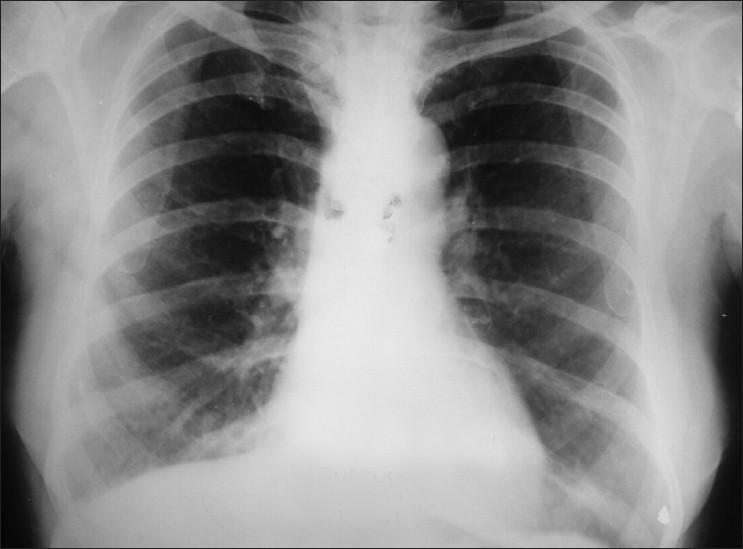

However, for diagnostic purposes, the X-ray technique is used. An X-ray must show ARDS, fluid inside the alveoli in the pair of lungs). In addition to that, a biopsy of lungs exhibiting damage of diffuse alveoli is also a requirement. If a diffuse damage alveolus is visible, the diagnosis is easy to perform.